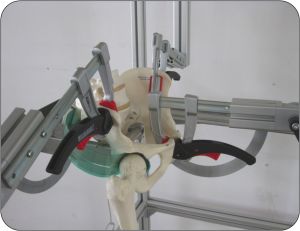

Tesis Doctoral

Estudio de presión articular de cadera, Influencia de la lesión del rodete acetabular.

El estudio muestra cómo la reparación del rodete acetabular logra restaurar las presiones articulares previas a la lesión del mismo